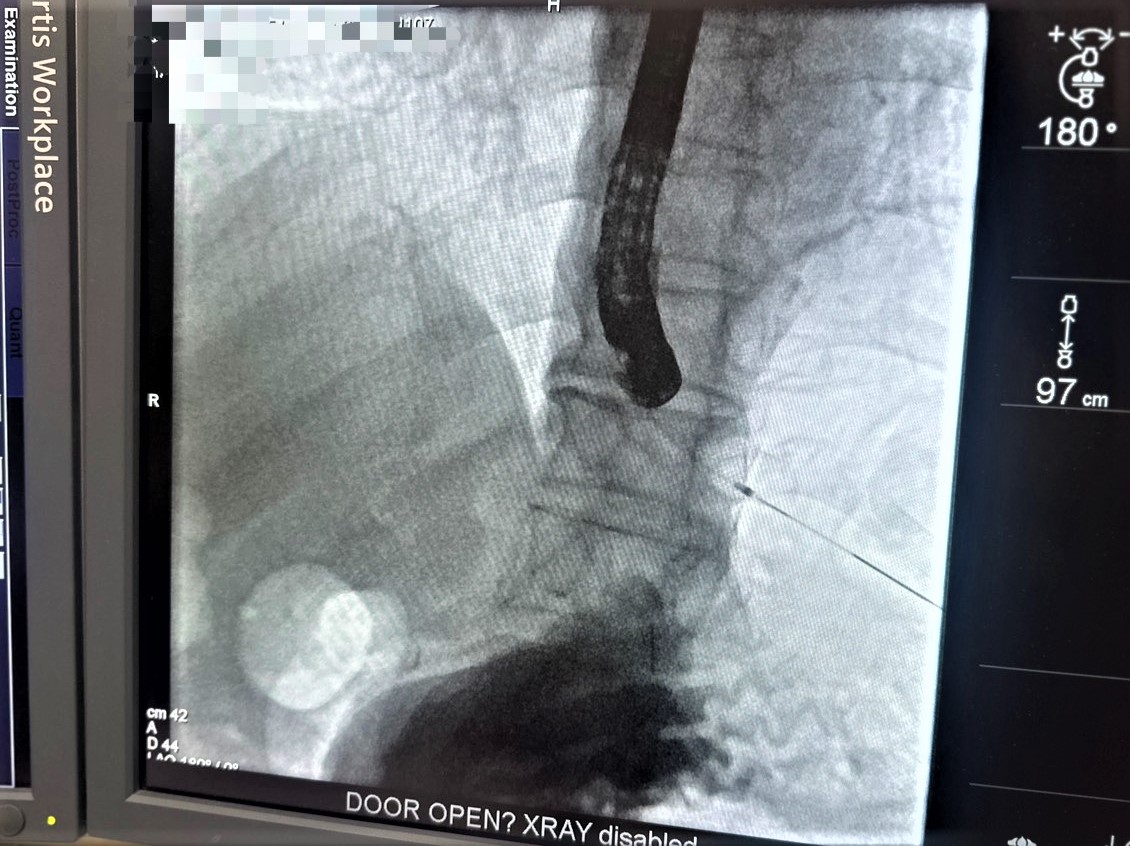

經檢查發現白血球、膽紅素與肝臟酵素明顯上升,腹部電腦斷層顯示總膽管被結石阻塞,確診為急性膽管炎,醫療團隊立即安排「經內視鏡逆行性膽胰管攝影術(ERCP)」,即時解除感染源,成功取出阻塞結石,使病情迅速穩定,避免進一步惡化成敗血症或休克。

呂家嘉醫師表示,經內視鏡逆行性膽胰管攝影術(ERCP)是目前處理急性膽管炎與總膽管結石最關鍵的治療方式之一,不只是取石,更是立即解除感染源的急救處置。手術透過內視鏡由口腔進入消化道,不需開腹即可將膽管開口擴大並取出結石,屬於微創治療,傷口小、恢復快,能在最短時間內改善感染與症狀。特別適合出現黃疸、發燒、膽道阻塞或感染徵象的患者,尤其對於高齡者、合併心臟病、糖尿病等慢性疾病,或不適合接受傳統開腹手術的族群而言,是風險相對較低、效益高的重要治療選擇。